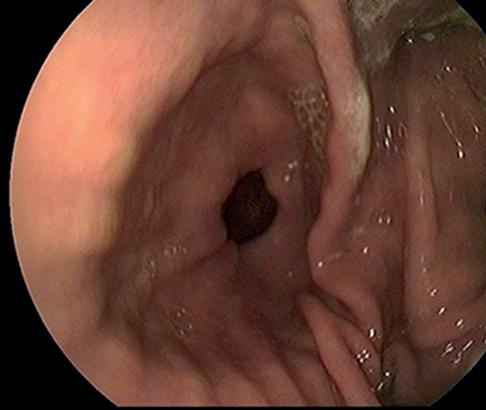

Diagnosis relies on visualisation of ulcers in the stomach region, and this is achieved with the use of a Gastroscope.

The apparatus is a three-metre-long flexible tube that is passed down the oesophagus via the nostril.

Acamera on the end of the scope is used to view the inside of the stomach, with the Gastroscope being connected to a computer screen.

AGastroscope gives us the ability to view the squamous, glandular and pyloric regions

of the stomach - all common areas for ulcers. During your horse’s scope, the vet can take video or photos of any area of interest. Prior to scoping, your horse's stomach will need to be empty, therefore fasting is carried out from the previous evening.

Asedative is used to help keep your horse relaxed and comfortable - the procedure is not painful but it can be a little unfamiliar for your horse.

Diagnosis of ulcers in the stomach region is achieved with the use of a Gastroscope.

AGastroscope examination of your horse’s stomach can provide quick information for treatment of gastric ulcers.